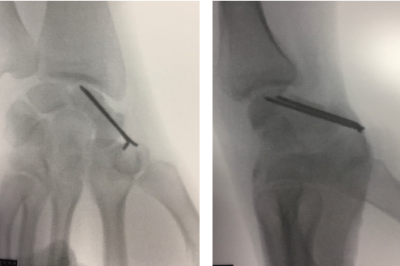

Résection simple de la pointe du radius / complète du poignet

Le traitement conservateur, c’est-à-dire la reconstruction et la conservation du scaphoïde, est possible. Il consiste à reconstruire le scaphoïde en retirant la zone de fibrose et en apportant de l’os de bonne qualité c’est-à-dire un greffon osseux. Ce traitement nécessite également une synthèse par broches ou vis. Le greffon peut être prélevé au niveau du radius (greffe vascularisée) ou au niveau de la crête iliaque (greffe non vascularisée).

Le matériel sera retiré à 3 mois après une imagerie de contrôle. Une rééducation doit être débutée ensuite.